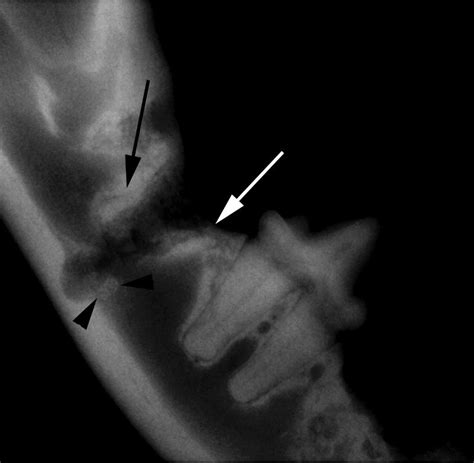

She'd been npo since 8 pm the previous evening and i didn't pick her up until about 4 pm. It causes infection and inflammation in the gums and the bone surrounding the tooth erodes, weakening the periodontal ligament that holds the tooth in place. Someone who needs a tooth extraction could. A dental extraction (also referred to as tooth extraction, exodontia, exodontics, or informally, tooth pulling) is the removal of teeth from the dental alveolus (socket) in the alveolar bone. Lip entrapment is a potential complication of maxillary canine tooth extraction and is most commonly seen in cats. Children are more likely than adults to have it, and playing roughly with a cat increases the chances of getting scratched. Periodontal disease (or gum disease) is a common cause of tooth loss in cats. We provide dog and cat tooth extraction treatments, see here for information on costs and the tooth extraction procedure.